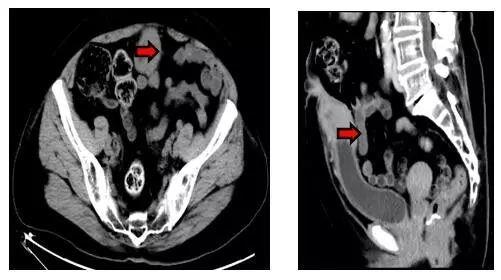

本例患者不是男性而是71歲女性,因“臍部溢液并下腹部紅腫硬塊”前來就診,之前也曾到過醫(yī)院但并未引起足夠的重視。家屬找到楊偉忠主任醫(yī)師后,經(jīng)仔細(xì)詢問病史并檢查病人,楊主任馬上診斷是臍尿管的慢性病變,并且高度懷疑腫瘤的可能性。立即給予下腹CT檢查報(bào)告為:“下腹部正中線區(qū)域臍-膀胱頂部之間軟組織腫塊影,性質(zhì)待定:臍尿管腫瘤?炎癥性病變?(見下圖)”。

入院后我們對(duì)患者進(jìn)行全面的身體狀況評(píng)估、認(rèn)真研究影像學(xué)資料確定病灶的范圍以及與鄰近臟器的關(guān)系、排查膀胱內(nèi)病變后,順利施行了標(biāo)準(zhǔn)的根治性切除手術(shù)。